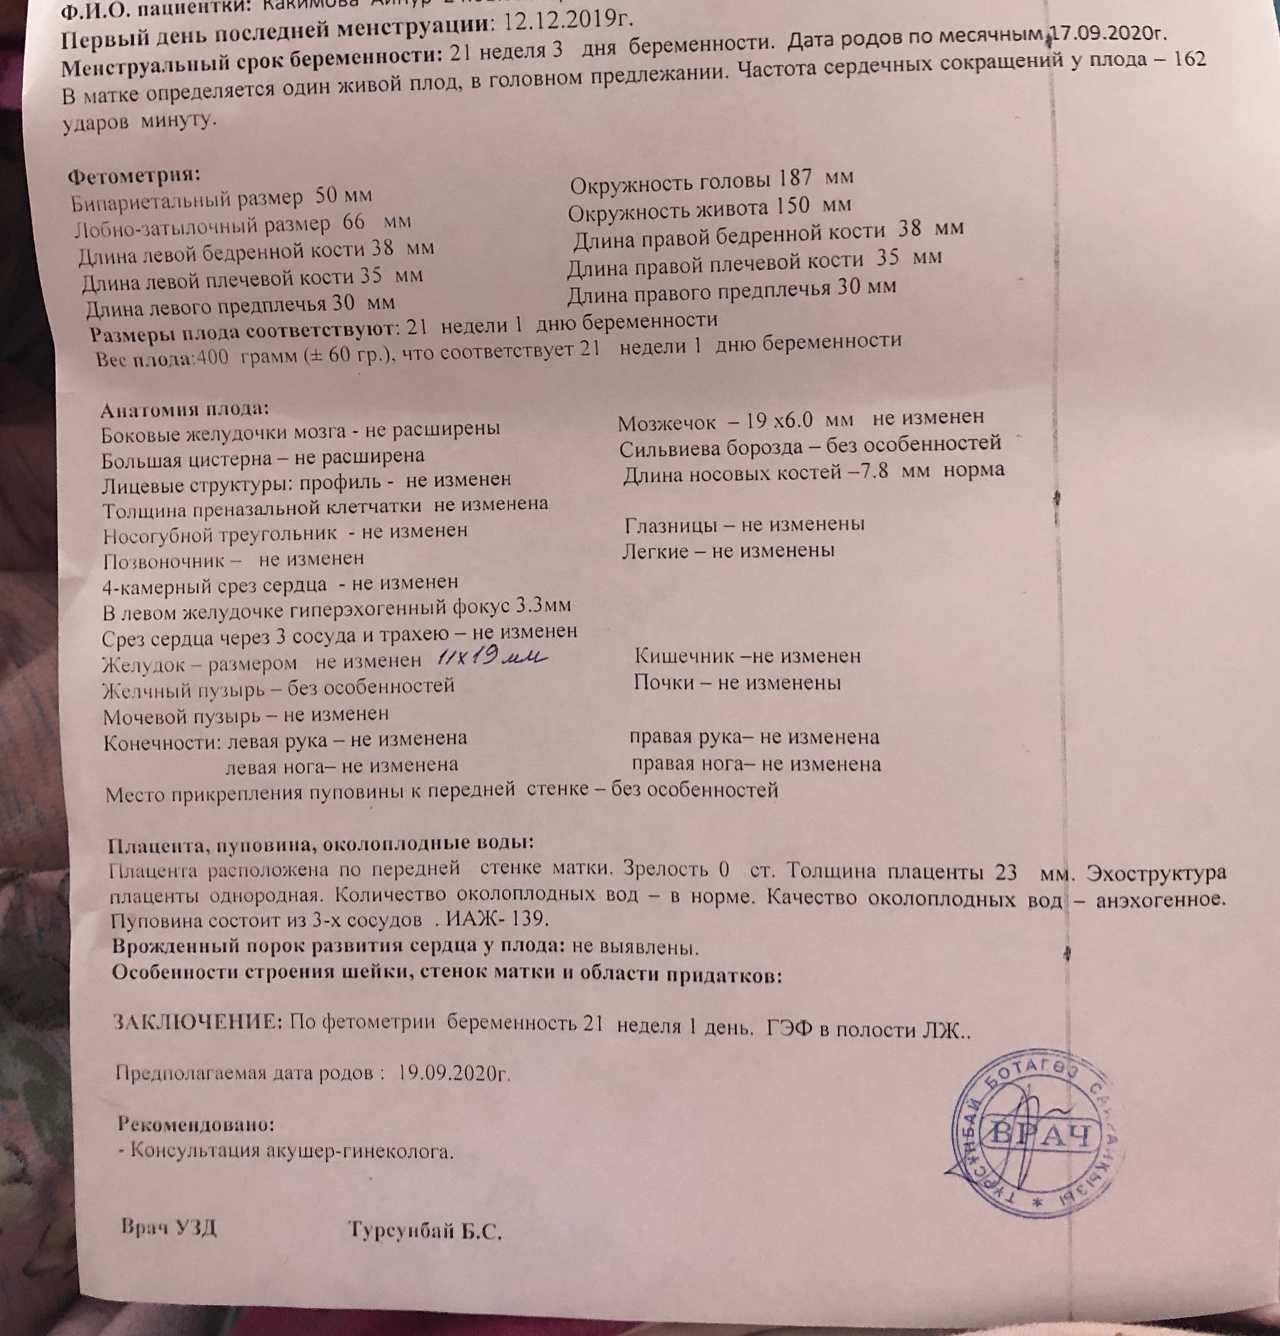

Нормы УЗИ 19-20 недель беременности